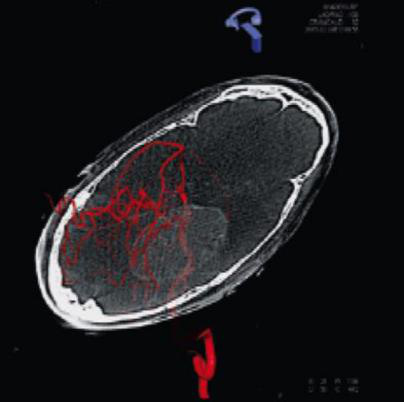

脑室引流通过DynaCT准确定位,将脑脊液引流管准确放置大脑内用于治疗脑积水、颅压升高、出血等外伤急症,避免误放引流管导致的二次外科手术。